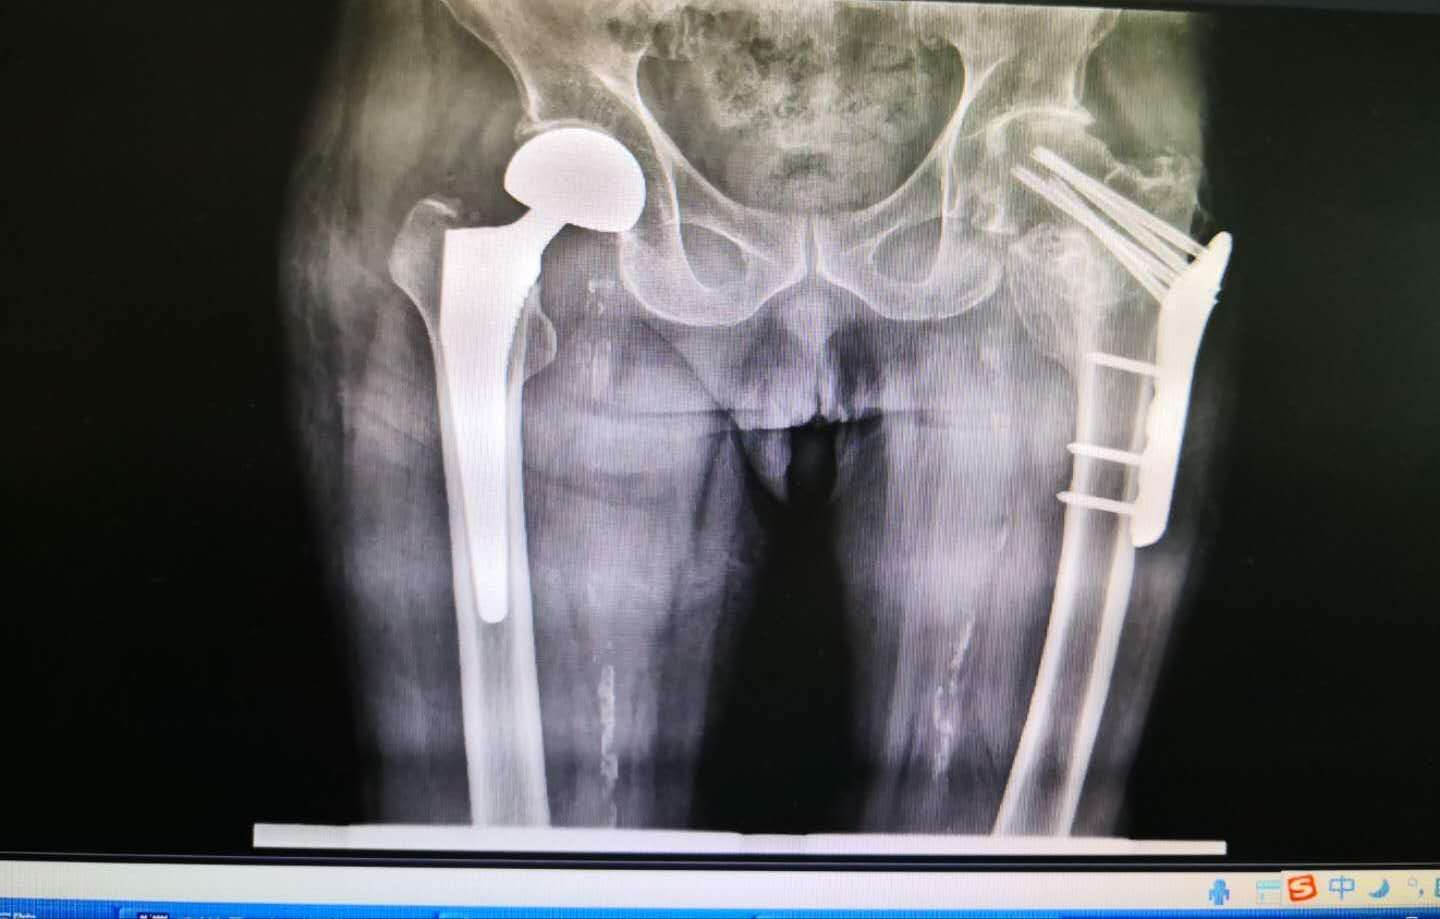

(术前)

伤情并不乐观,左侧股骨颈骨折,Ⅲ型及左侧锁骨远端骨折。虽然患者上肢骨折可以选择保守治疗,但下肢平时经常行走,股骨颈骨折不治?回家卧床?行吗?

患者家属慕名来到沈阳医学院附属第二医院皇姑院骨外一科就诊。骨外一科陈铁主任带领陈玉楼副主任医师及团队成员在呼吸内科张永红医生会诊指导下,麻醉科魏之先主任及郑玉国医生麻醉配合下,于大年初三成功完成一例人工双动股骨头置换手术。手术成功后,患者转至重症医学科继续治疗。

(术后)